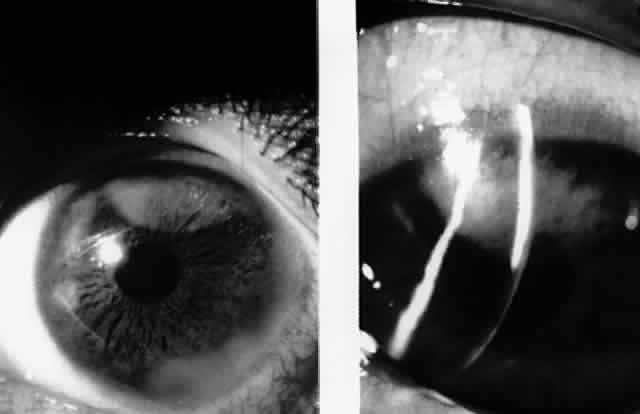

Fig. 4. Multifocal deep peripheral corneal stromal infiltrates in a 17-year-old man. (Matoba AY, Wilhelmus KR, Jones DB: Epstein-Barr viral stromal keratitis. Ophthalmology 93:746, 1986)

In 1990, Pflugfelder and associates reported a 66-year-old woman with bilateral, pleomorphic, ring-shaped, anterior stromal opacities which developed 3 months after initial onset of concurrent bilateral, dendritic epithelial keratitis (Fig. 5).74 Dendritic epithelium removed by impression cytology at the second recurrence of epithelial disease bound monoclonal antibody to EBV early antigen-diffuse and contained EBV genomic sequences as shown by PCR. Corneal epithelial cultures for HSV were negative on two occasions. EBV serology test did not indicate acute infection, and thus confirmed the earlier impression of Matoba and associates, that EBV keratitis may follow viral reactivation from the chronic carrier state.

Fig. 5. Peripheral corneal dendrite (arrows) in a 66-year-old woman who later developed ring opacities of the anterior corneal stroma.